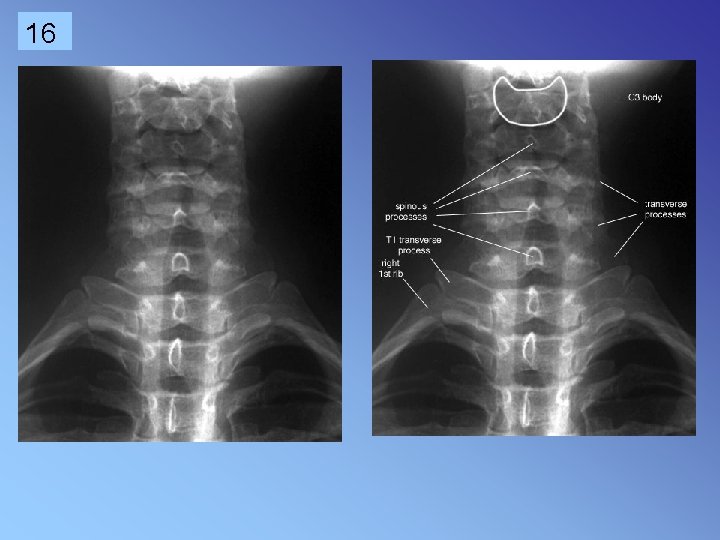

16